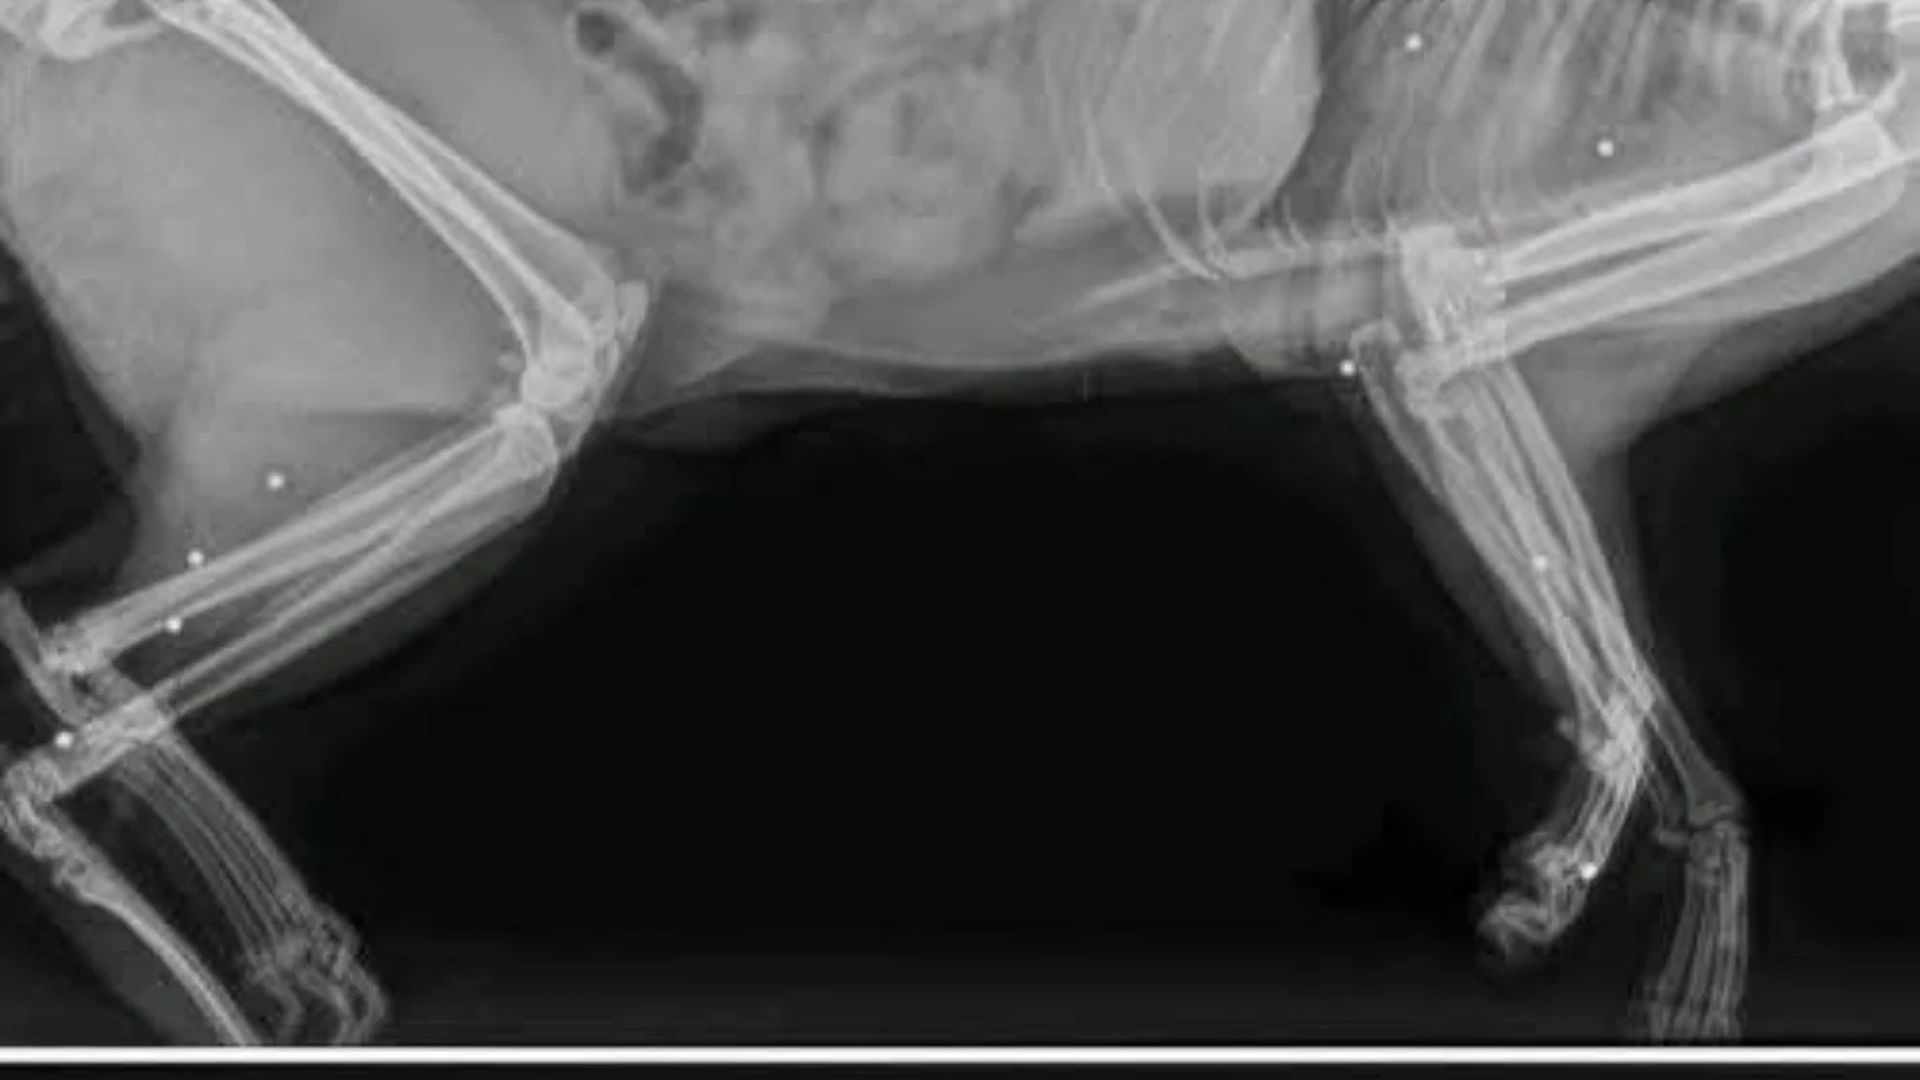

Valentín, un gato que deambulaba por las calles de Plasencia, apareció a mediados de enero herido. Fue trasladado de urgencias al veterinario pensando que se trataba de un atropello, pero las radiografías arrojaron hasta donde puede llegar la crueldad de algunos individuos.

El animal hacía recibido el impacto de 19 proyectiles por todo su cuerpo. Al parecer, fue disparado con una carabina de aire comprimido. Se hizo todo los posible por salvar su vida, pero los proyectiles hicieron imposible que sobreviviera por la heridas en pulmón, columna y cabeza, tal y como ha denunciado la protectora Adopta Plasencia, que pide colaboración ciudadana para evitar que se repitan más casos como el de Valentín.